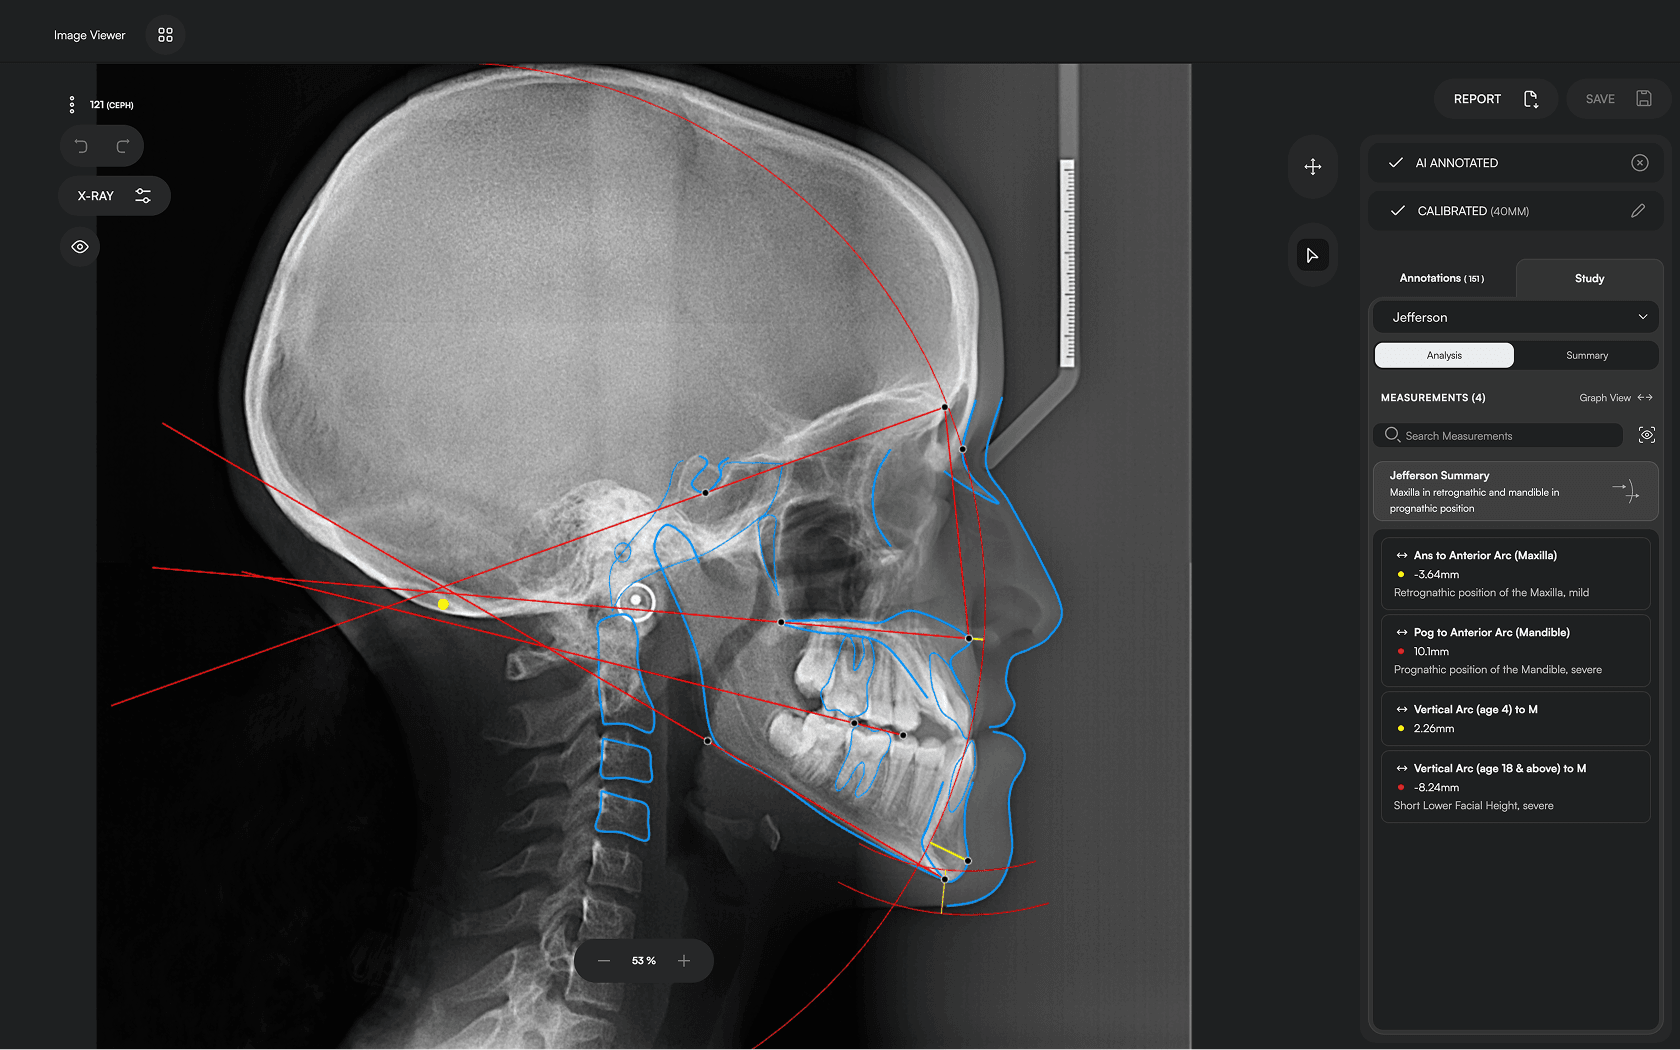

Diverse Analysis

Access automated studies like Steiner and Jefferson to assist in clinical assessment and enhance case evaluations.

Powerful Insights

Experience a comprehensive assessment of skeletal, dental, and soft tissue discrepancies.

Clear Reporting

Create concise, clear reports to build confidence, enhance patient

communication and ensure transparency.